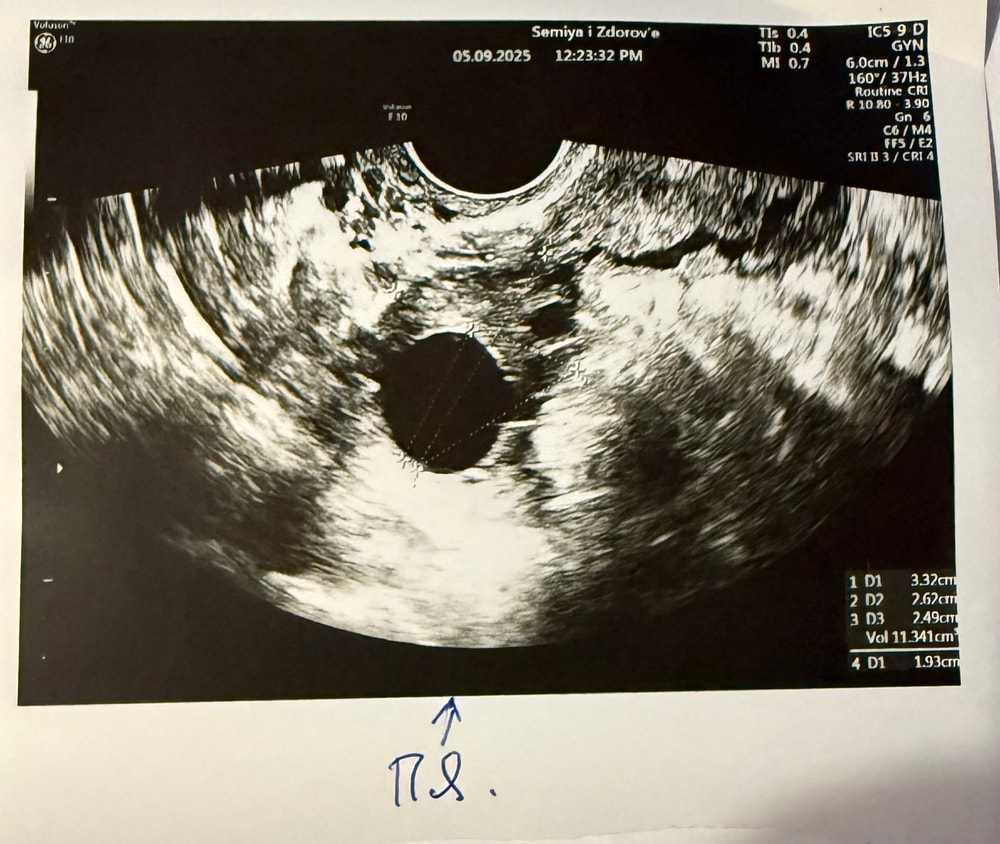

05.09. (16 ДЦ), пошла на узи, не смогла попасть в свою клинику, в ЛЯ ничего нет, в ПЯ ДФ 19,3 мм.